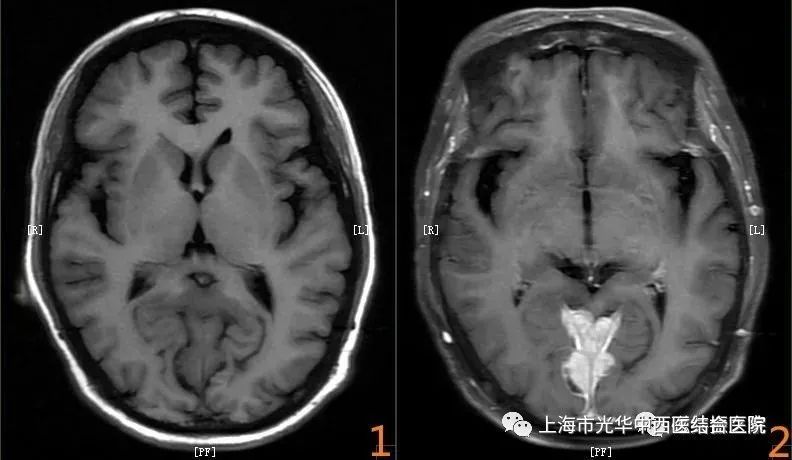

磁共振平扫就是利用人体正常组织和病变组织所含的H离子不同磁共振信号不同来成像的,通过多个序列成像以显示病变组织的位置、大小、数目、形态及信号变化用于诊断疾病。但是有些病变比如说消化系统以及颅脑的一些肿瘤,平扫时它们的磁共振信号接近正常组织的信号,在图像上只能观察到某某区域稍有异常,而不能做出精准诊断,也有一些不同的病变信号接近造成鉴别诊断上的困难,或者病灶周围的结构显示欠清,这时就需要做磁共振增强扫描,通过静脉注射造影剂来提高病变组织和正常组织的信号对比度、强化-时间信号曲线变化做出精准的诊断,为临床治疗提供可靠的依据。总而言之一句话:磁共振增强检查可以看的更多更清楚,有利于疾病定位及定性。

注:图1是平扫图像,图2是增强图像